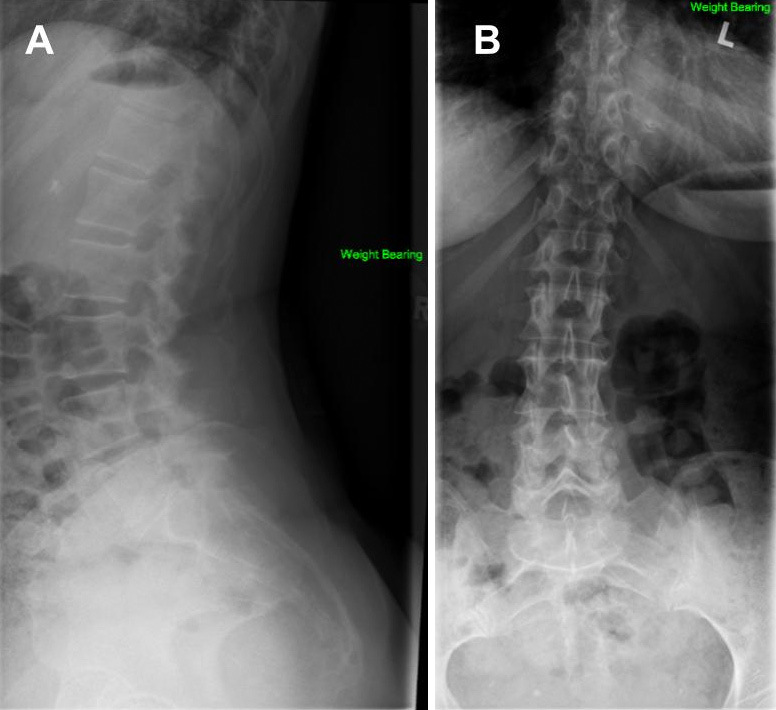

Severe Spinal Stenosis Secondary to a CREST Syndrome Related Calcific Deposit: A Case Report.